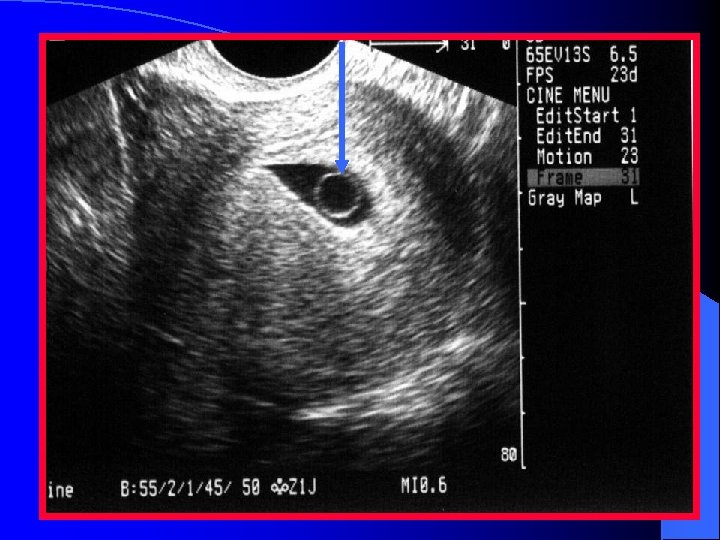

Gestational Sac l Anechoic area within the uterus surrounded by two bright echogenic rings – Decidua vera (the outer ring) – Decidua capsularis (the inner ring) l This is referred to as the double decidual sac sign (DDSS)

Yolk Sac l First embryonic structure that can be detected sonographically l Visualized approximately 5 -6 weeks after the last menstrual period l Bright, ring like structure within the GS l Should be readily seen when the GS sac is greater than 10 mm (using EVS)